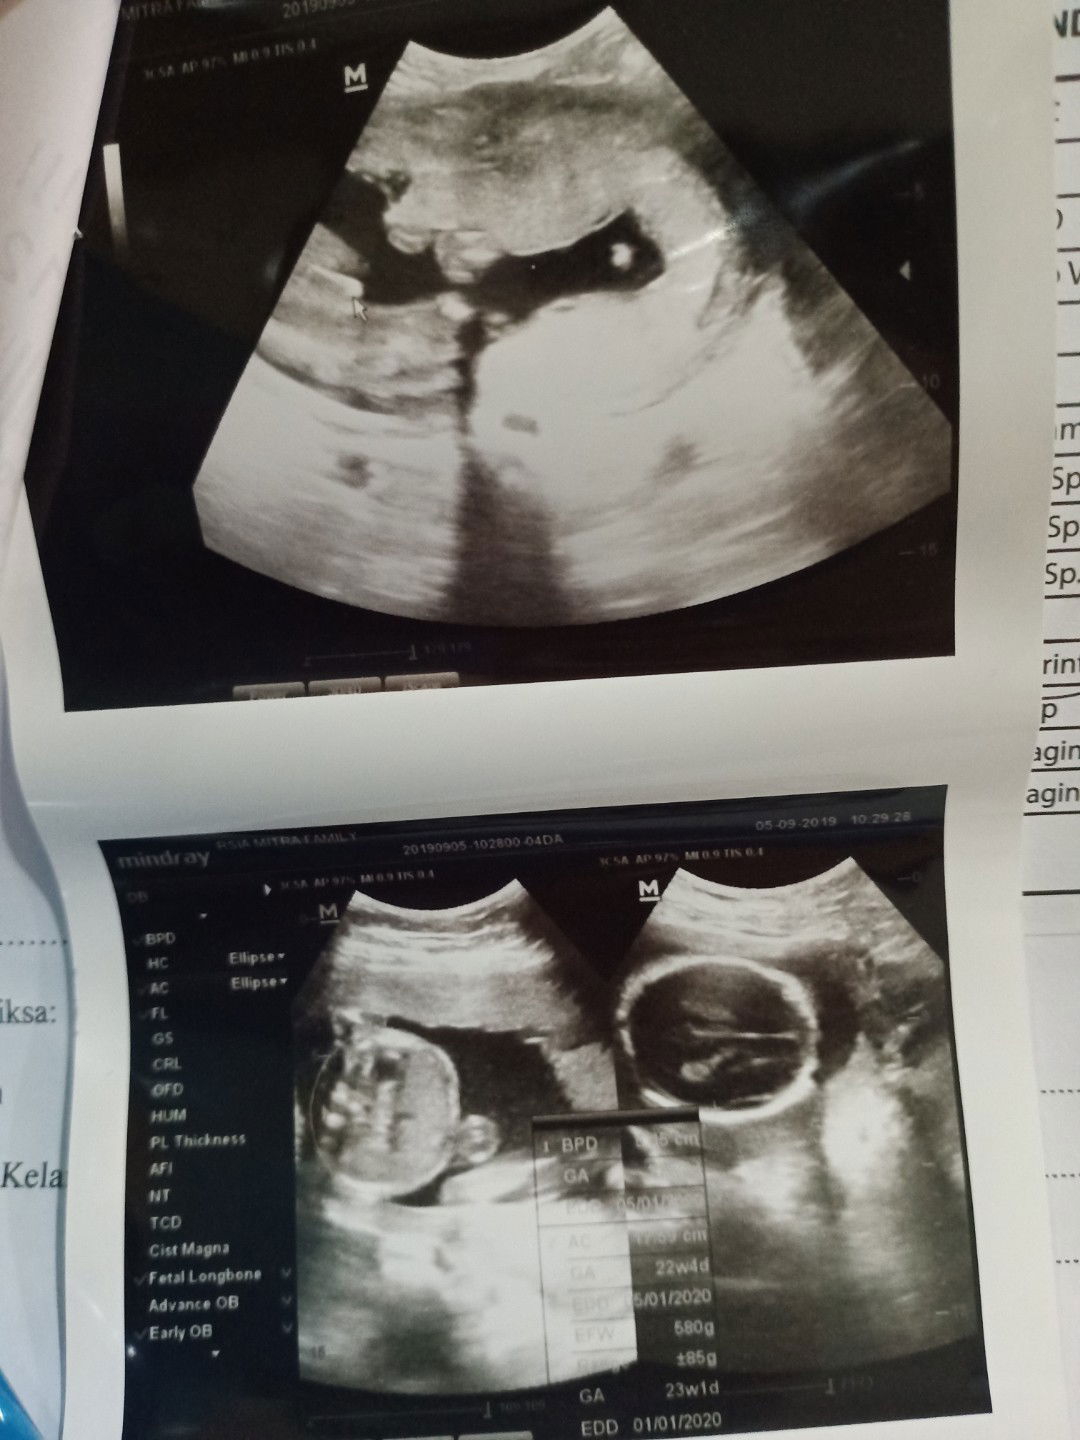

Bunda... Ada yg sama ga kaya gini?? Jd... Klo d liat d foto hasil usg yg paling atas.. Ada tanda panah warna putih kecil, nah kata dokter itu JK ny laki-laki.... Alhamdulillah klo iya. . yg penting adik bayi sehat... ?